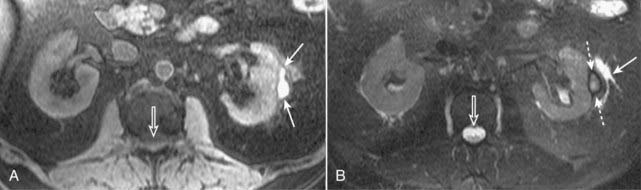

If the fluid is dark, then you are probably looking at a T1-weighted sequence (Fig. 20-1A).

If this fluid is bright, then chances are you are looking at a T2-weighted image (Fig. 20-1B).

Figure 20-1 Normal T1-weighted and T2-weighted axial images of the abdomen.

Because cerebrospinal fluid is similar to water in density, it appears dark on the T1-weighted image (A) (solid white arrow), and bright on the T2-weighted image (B) (open white arrow). Subcutaneous fat (dotted white arrows) and intraabdominal fat (dotted black arrows) are bright on both T1-weighted and T2-weighted images.